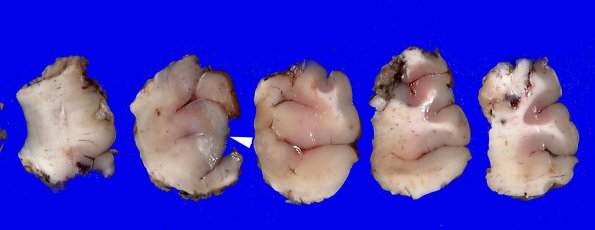

17A1 Tuber (Case 17) Gross 1

The gross neurosurgical specimen showing the tuber (arrow) from the external surface.